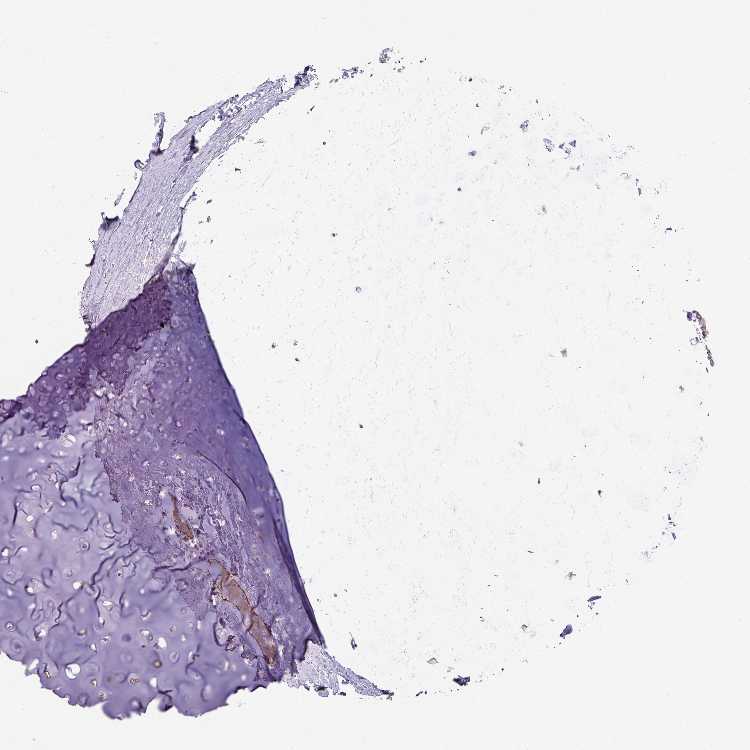

ADIPOSE TISSUE - Antibody stainingi

Antibody staining in the annotated cell types in the current human tissue is reported as not detected, low, medium, or high, based on conventional immunohistochemistry profiling in selected tissues. This score is based on the combination of the staining intensity and fraction of stained cells.

Each image is clickable and will lead to virtual microscopy that enables deeper exploration of all samples and also displays staining intensity scores, fraction scores and subcellular localization as well as patient and tissue information for each sample.

Antibody HPA052352

Adipocytes Not detected